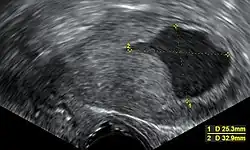

Transvaginal ultrasound to examine the endometrial thickness in women with postmenopausal bleeding is increasingly being used to aid in the diagnosis of endometrial cancer in the United States.[40] In the United Kingdom, both an endometrial biopsy and a transvaginal ultrasound used in conjunction are the standard of care for diagnosing endometrial cancer.[17] The homogeneity of the tissue visible on transvaginal ultrasound can help to indicate whether the thickness is cancerous. Ultrasound findings alone are not conclusive in cases of endometrial cancer, so another screening method (for example endometrial biopsy) must be used in conjunction. Other imaging studies are of limited use. CT scans are used for preoperative imaging of tumors that appear advanced on physical exam or have a high-risk subtype (at high risk of metastasis).[41] They can also be used to investigate extrapelvic disease.[17] An MRI can be of some use in determining if the cancer has spread to the cervix or if it is an endocervical adenocarcinoma.[41] MRI is also useful for examining the nearby lymph nodes.[17]